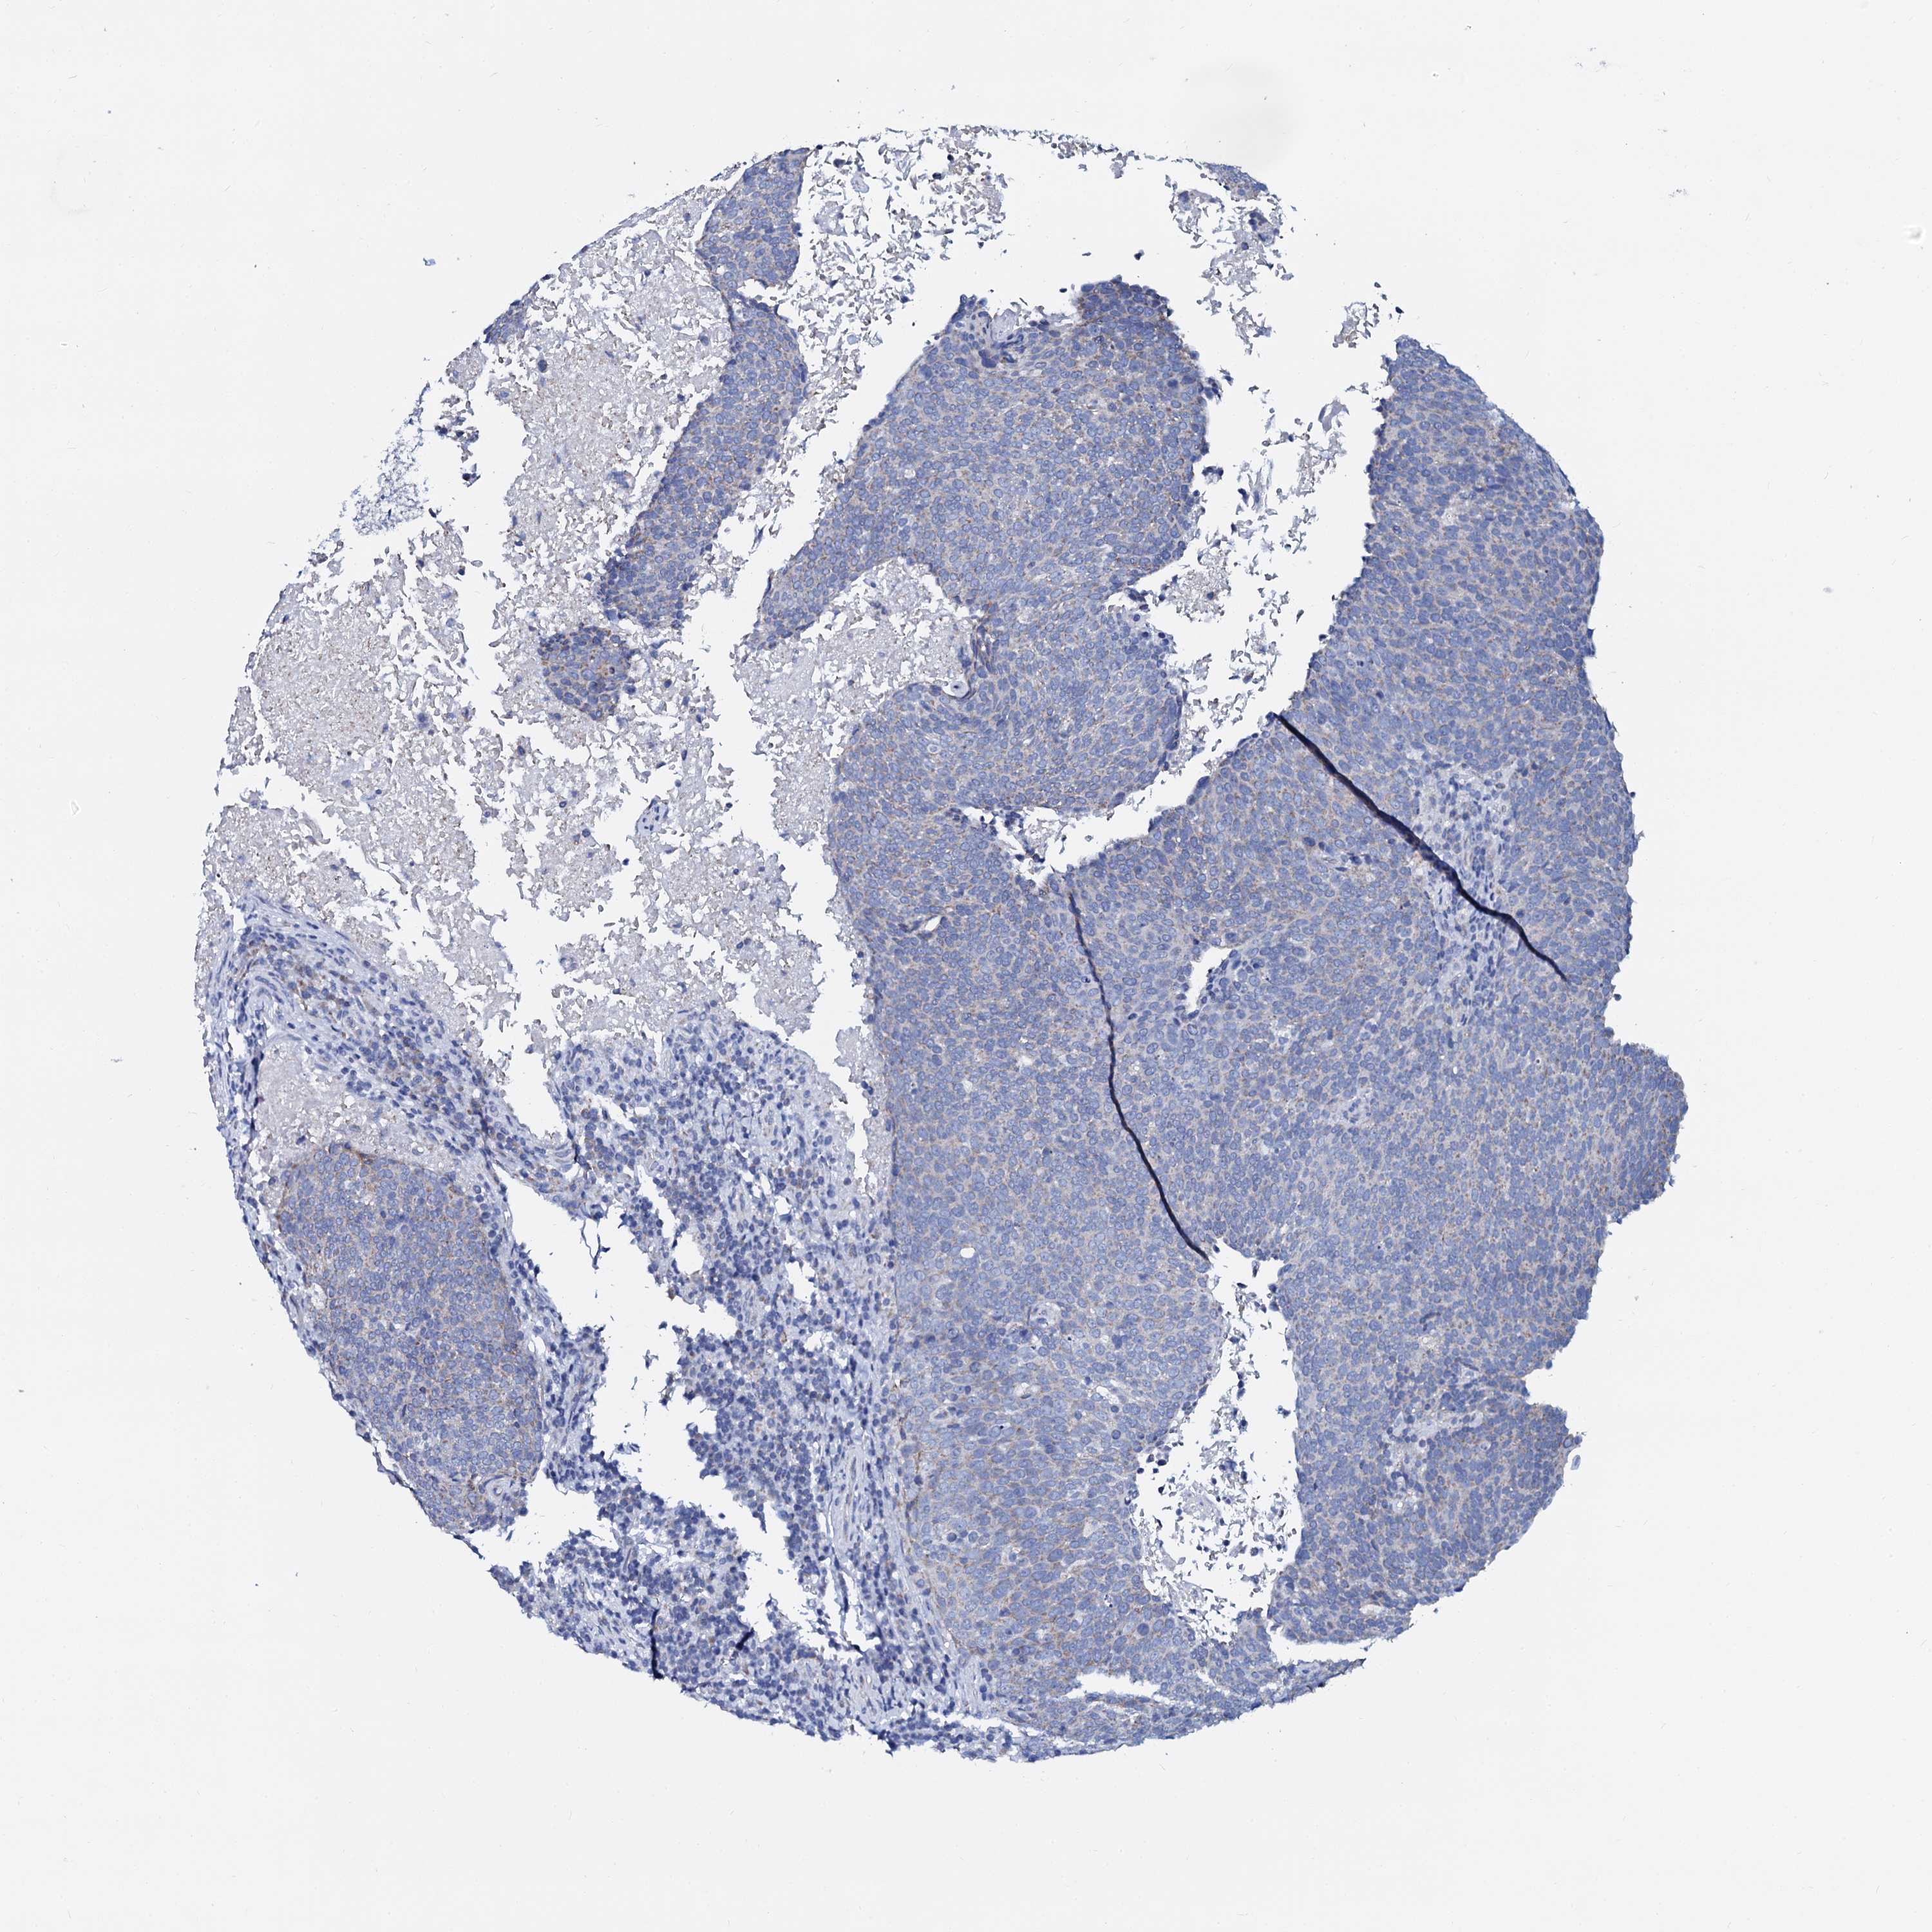

HEAD AND NECK CANCER - Protein expressioni

A mouse-over function shows sample information and annotation data. Click on an image to view it in a full screen mode. Samples can be filtered based on level of antibody staining by selecting one or several of the following categories: high, medium, low and not detected. The assay and annotation is described here.

Antibody stainingi

Antibody staining in the annotated cell types in the current human tissue is reported as not detected, low, medium, or high, based on conventional immunohistochemistry profiling in selected tissues. This score is based on the combination of the staining intensity and fraction of stained cells.

Each image is clickable and will lead to virtual microscopy that enables deeper exploration of all samples and also displays staining intensity scores, fraction scores and subcellular localization as well as patient and tissue information for each sample.

Antibody HPA038940

Staining

High

Medium

Low

Not detected

Intensity

Strong

Moderate

Weak

Negative

Quantity

>75%

75%-25%

<25%

None

Location

Nuclear

Cytoplasmic/membranous

Cytoplasmic/membranous,nuclear

Squamous cell carcinoma, NOS

Squamous cell carcinoma, metastatic, NOS